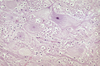

Lamb. Mdx? Etiology?

Cyclopia/Synophthalmos

Incomplete seperation of the orbits during embyrogenesis

Etiology: Veratrum Californicum ingestion on day 14

Determine cause via thourough history